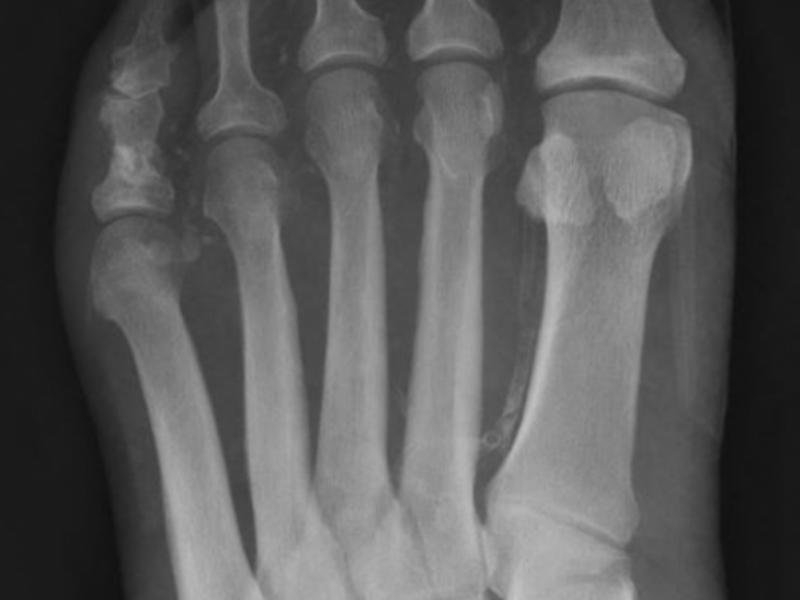

A 65 yo male PMH HTN, HLD presents with left foot pain and